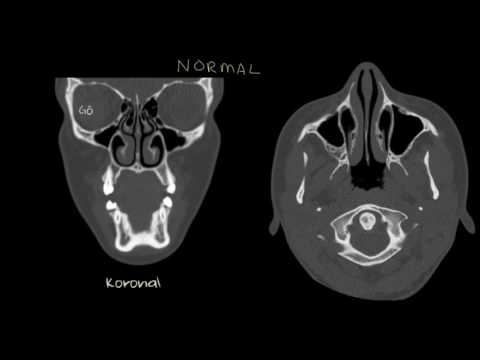

Nazal Polipler